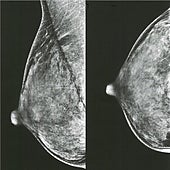

Estas mutaciones marcan si un cáncer mama resiste a la terapia en las más jóvenes

Iniciar sesiónUn estudio que se publica en la revista «Science Advances» ha descubierto que en mujeres jóvenes, ciertas mutaciones genéticas están asociadas con un cáncer de mama resistente al tratamiento. Sin embargo, dichas mutaciones no están relacionadas con el cáncer de mama resistente al tratamiento ... en mujeres mayores. Los hallazgos, podrían ayudar a mejorar la medicina de precisión y sugerir una nueva forma de clasificar el cáncer de mama.

La investigación se centró principalmente en el cáncer de mama ER+/HER2-, que es una de las formas más comunes. Por lo general, se trata con terapias hormonales, pero para algunas pacientes, estos tratamientos no funcionan.